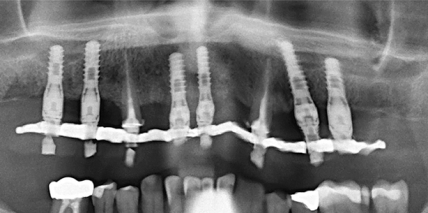

Definitive Sofortversorgung eines ­parodontal kompromittierten Patienten mit sechs Implantaten

Jahr 2016, Ausgabe 03, Seite 26 Autoren: Dr. Horst Schubert, Dr. Jörg Huberth, ZTM Michael Fößel